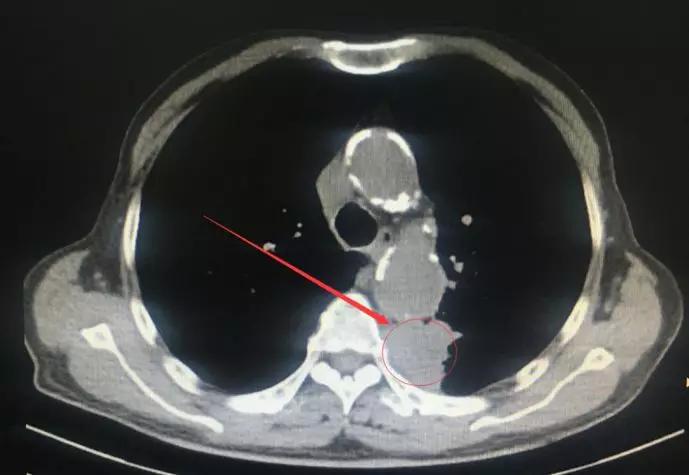

这引起了医生的重视,因为这与肺癌的症状十分相似,所以建议暂缓胃镜检查,建议先做个CT检查,结果不出所料,发现了疑似肺部肿瘤。

老张的肺部CT

后经穿刺病理,最终诊断为:低分化肺腺癌!